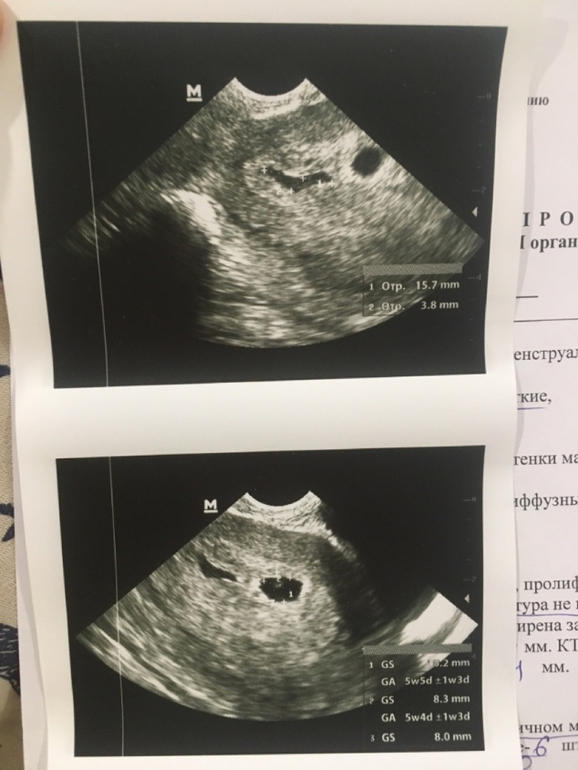

Результаты: УЗИ, КТГ, доплера, скринингаДобрый день, сходила сегодня на первое УЗИ. Срок 5 недель 4 дня. Беременность маточная, но обнаружили гематому, сказали, что надо идти к гинекологу, чтоб назначили лечение, чтоб гематома не росла. Записалась на понедельник.